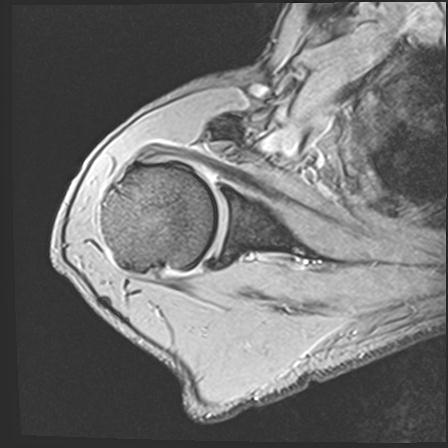

60058 3/9 11/4 右肩 2R+MRI 73歳男性 肩腱板損傷